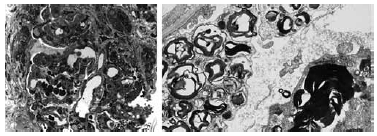

Considerando as imagens a seguir, obtidas por microscopia ótica e microscopia eletrônica, assinale a alternativa que apresenta a descrição da patogênese da doença representada na biópsia renal em questão.